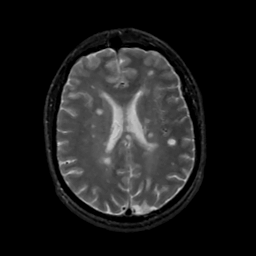

MR Study #14, June 2, 1991 -- Slice #31

[Home][Help][Clinical][Tour 1][Tour 2] Slice 31